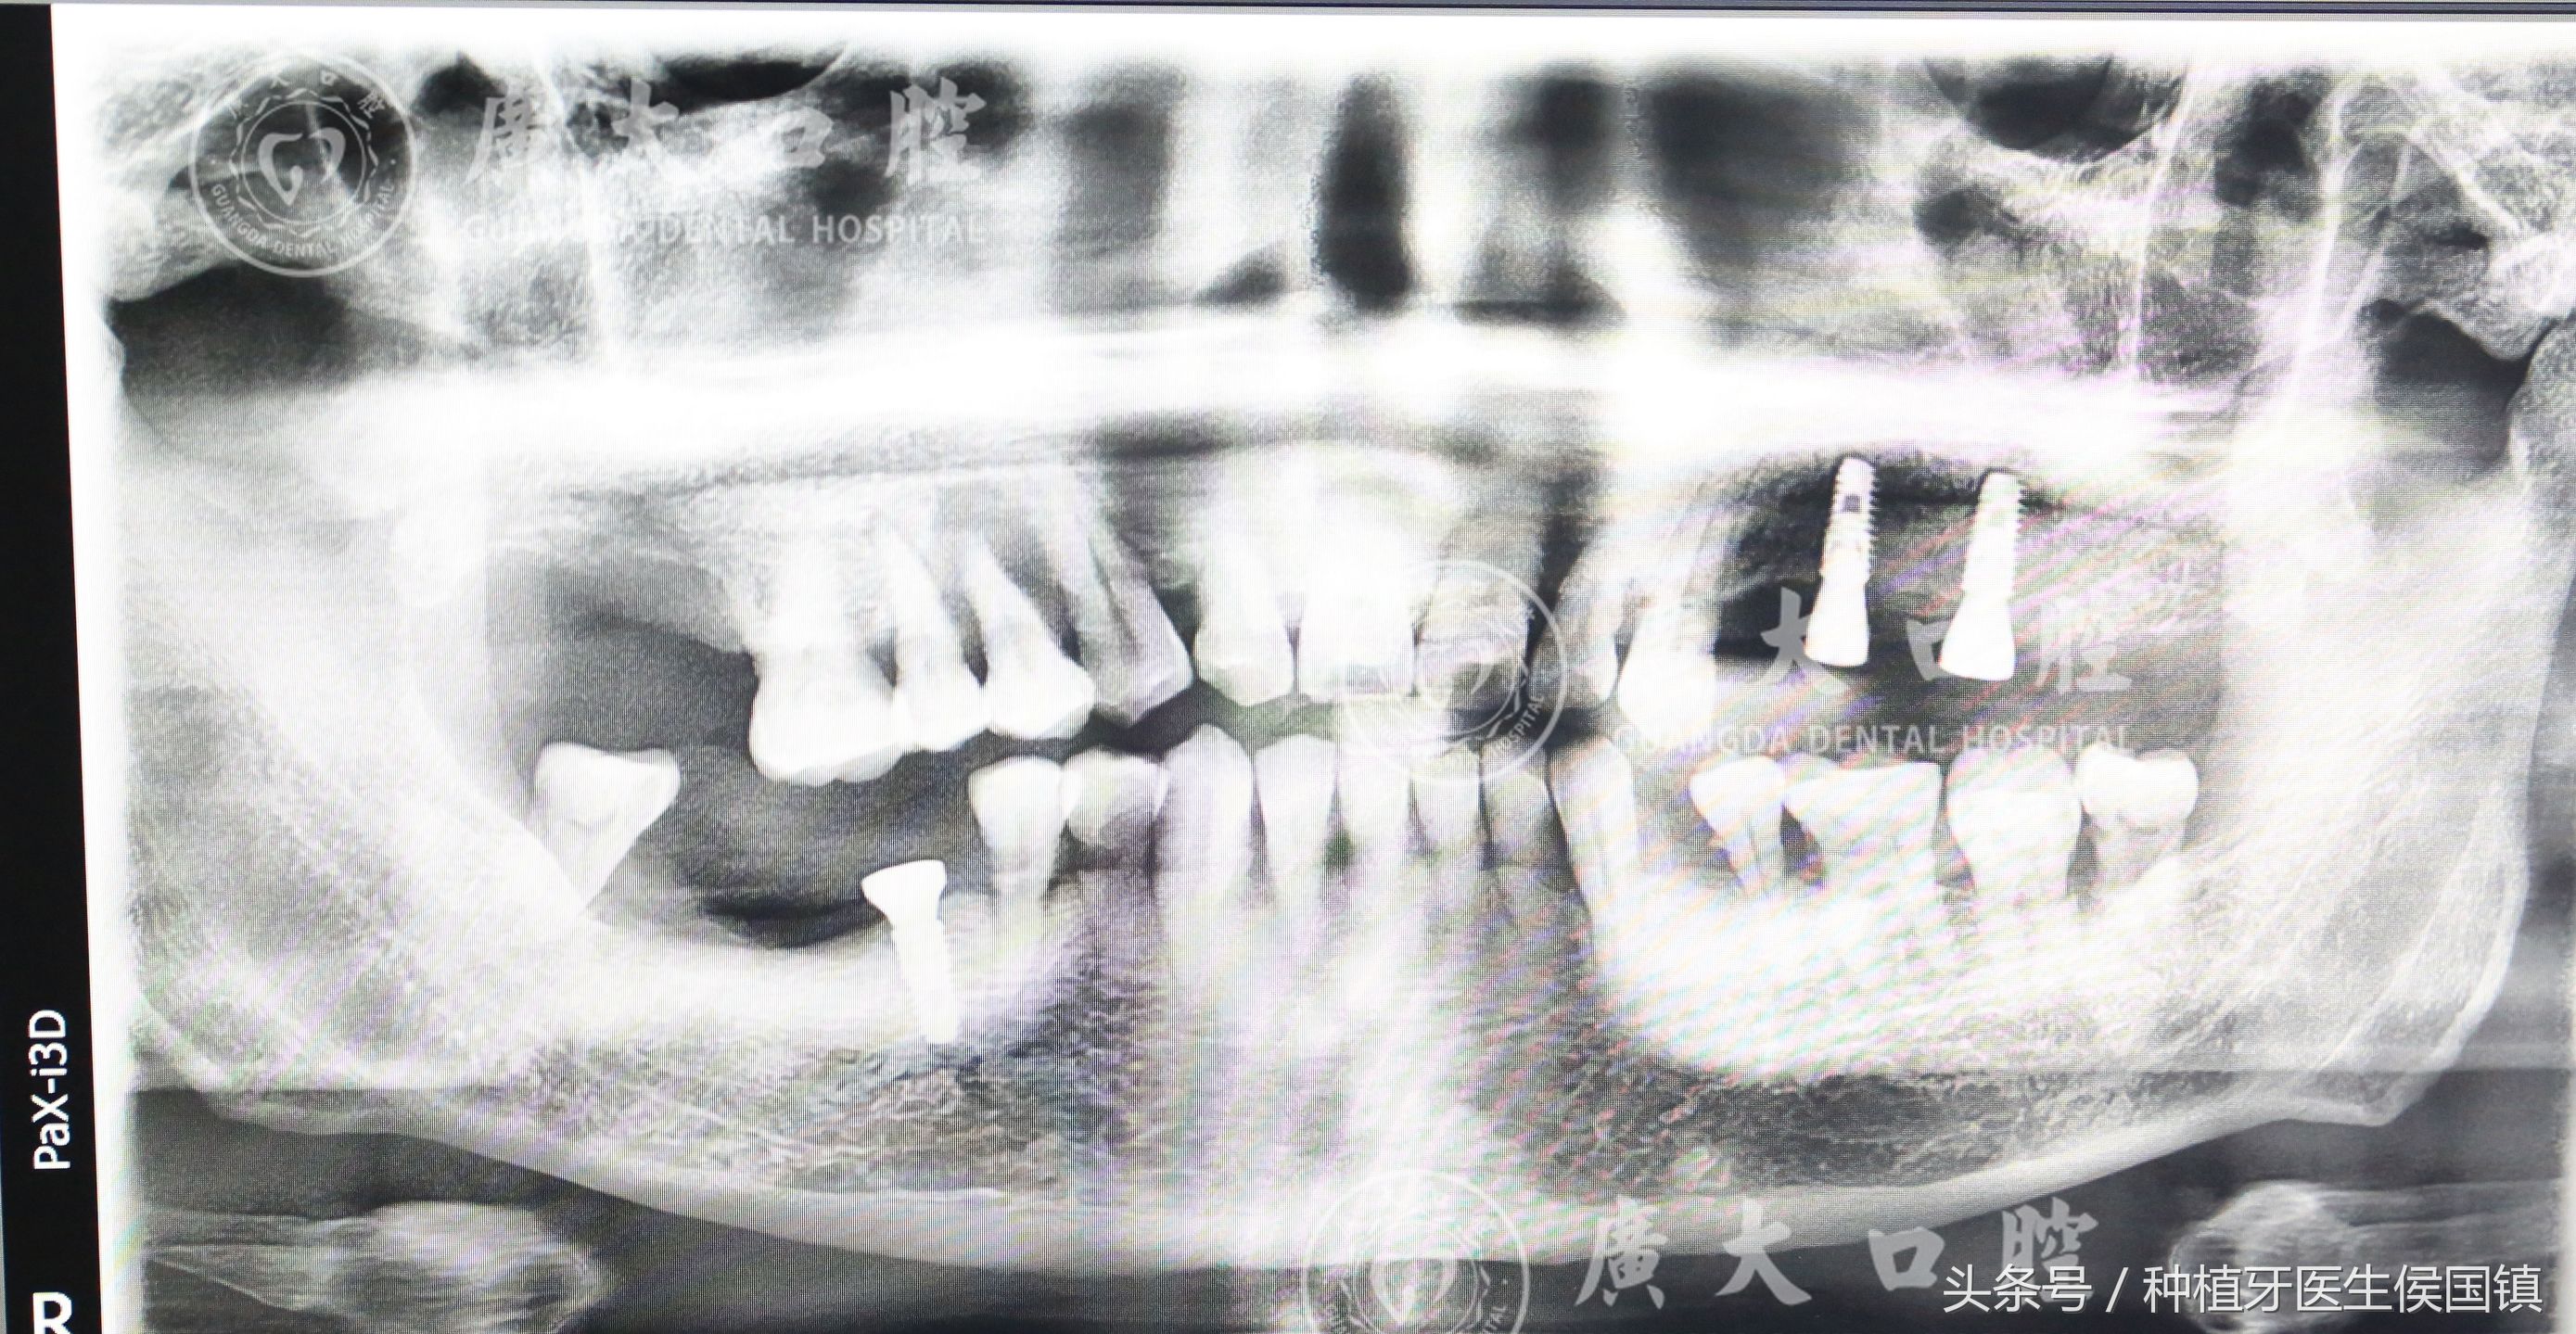

植入种植体后

种植牙过程